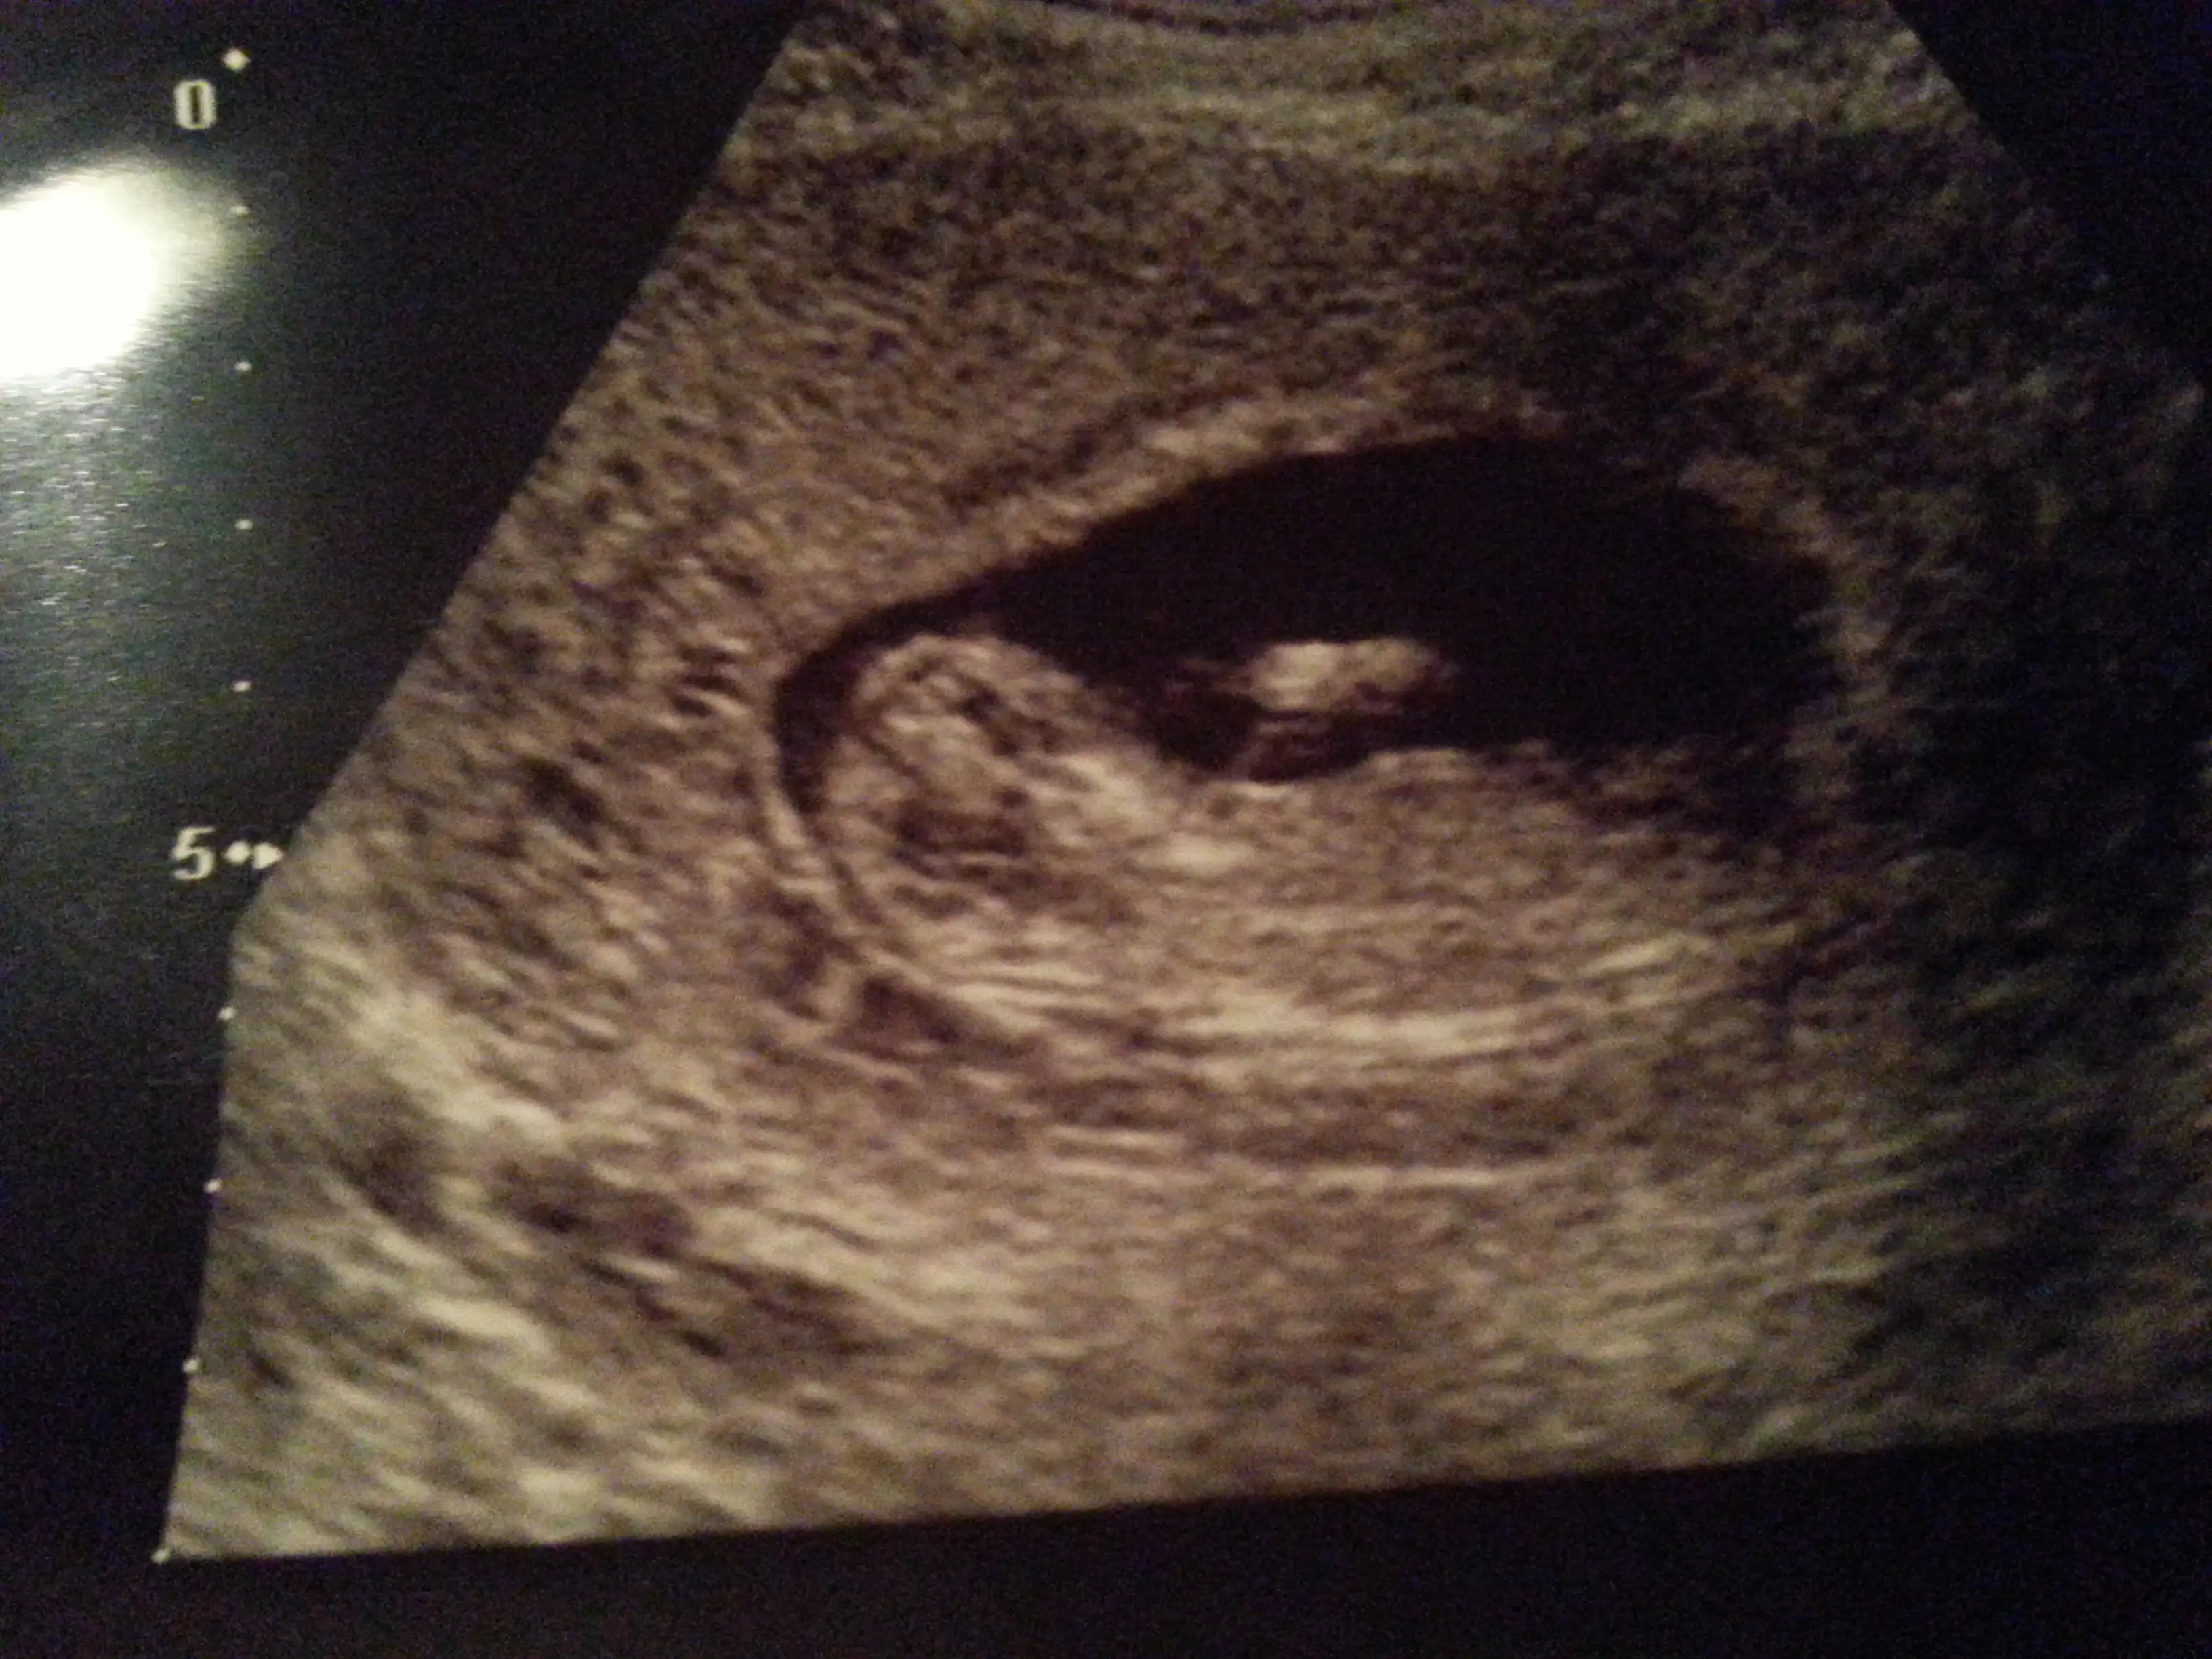

İlk iki görüntü ense kalınlığına bakmak için girdiğim ultrason görüntüleri alttaki diğer 2 görüntüyse normal doktor kontrolündeki ultrason görüntüleri ve ikisi de aynı gün ve tam 12 haftalıkken ve tekrar teşekkür ediyorum